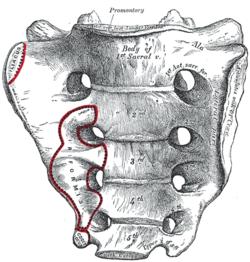

Gray95.png

Sacrum, pelvic surface. (The two columns of four holes are the intervertebral foramina of sacrum, visible but not labeled.)